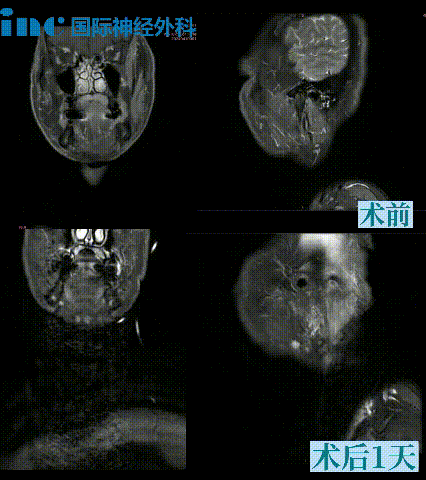

INC巴特朗菲教授示范手术期间,多名颈静脉孔区肿瘤患者获得成功治疗。其中一例为38岁东南亚男性患者Norodom,诊断为颈静脉孔区神经鞘瘤,临床表现为频繁呛咳、颈部右倾、右肩肌张力增高、持续右侧颈痛及体位受限。经跨国求医,术后第一天ICU查房显示患者意识清醒,吞咽功能与肢体活动正常。

另一例为15岁青少年患者小凯,临床表现为声音嘶哑、扁桃体炎、耳痛及持续性头痛。药物治疗初期部分缓解症状但易反复。一月后复查发现颈静脉孔区神经鞘瘤生长。在巴教授主刀下行肿瘤全切术,术后恢复良好:术后2个月精神状态显著改善;术后6个月影像学评估显示肿瘤完全切除,脑干、血管及颅底结构保护完好,嗓音功能明显恢复;术后1年经耳鼻喉科专家评估及发声训练,声带问题显著改善。